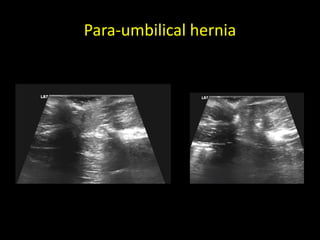

Para-umbilical hernia